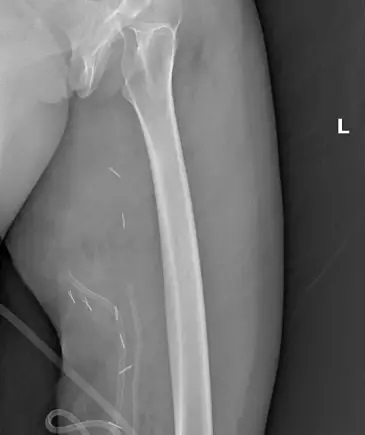

Muayenede yumuşak doku kitlesi olduğu değerlendirilen şişliğin alınması için Ortopedi ve Travmatoloji Anabilim Dalı Öğretim Üyesi Prof. Dr. Emin Özkul ve ekibi tarafından ameliyat kararı verildi. Yaklaşık 2 saat süren operasyonla kitlenin çıkarıldığı, kitlenin 5 kilo 668 gram geldiği belirtildi.

Bu hasta da 3 yıl önce fark edilmiş küçük bir kitle, zamanla çok büyük boyutlara, yaklaşık 6 kiloya varan boyutlara varmıştı. Neredeyse bütün bacak boyu yayılan bir kitlesi mevcuttu.

Bu kadar büyümenin şöyle sıkıntıları oluyor, kişinin bacağında, kolunda fonksiyon kaybına, yeri geliyor ekstremite kaybına, yani bacağını kaybetmesine yol açabilecek sıkıntılara yol açıyor. Küçükken bunlarla baş etmek daha kolay.

Kişinin ekstremitesinde, bacağında, kolunda bir sıkıntı yaratmadan bunları telafi etmek, bunları alıp çıkartmak, ameliyatla bunları tedavi etmek daha kolayken bu boyutlara vardığında kişinin bacağında, kolunda fonksiyon kaybı, sakatlık riski çok yüksek oluyor.